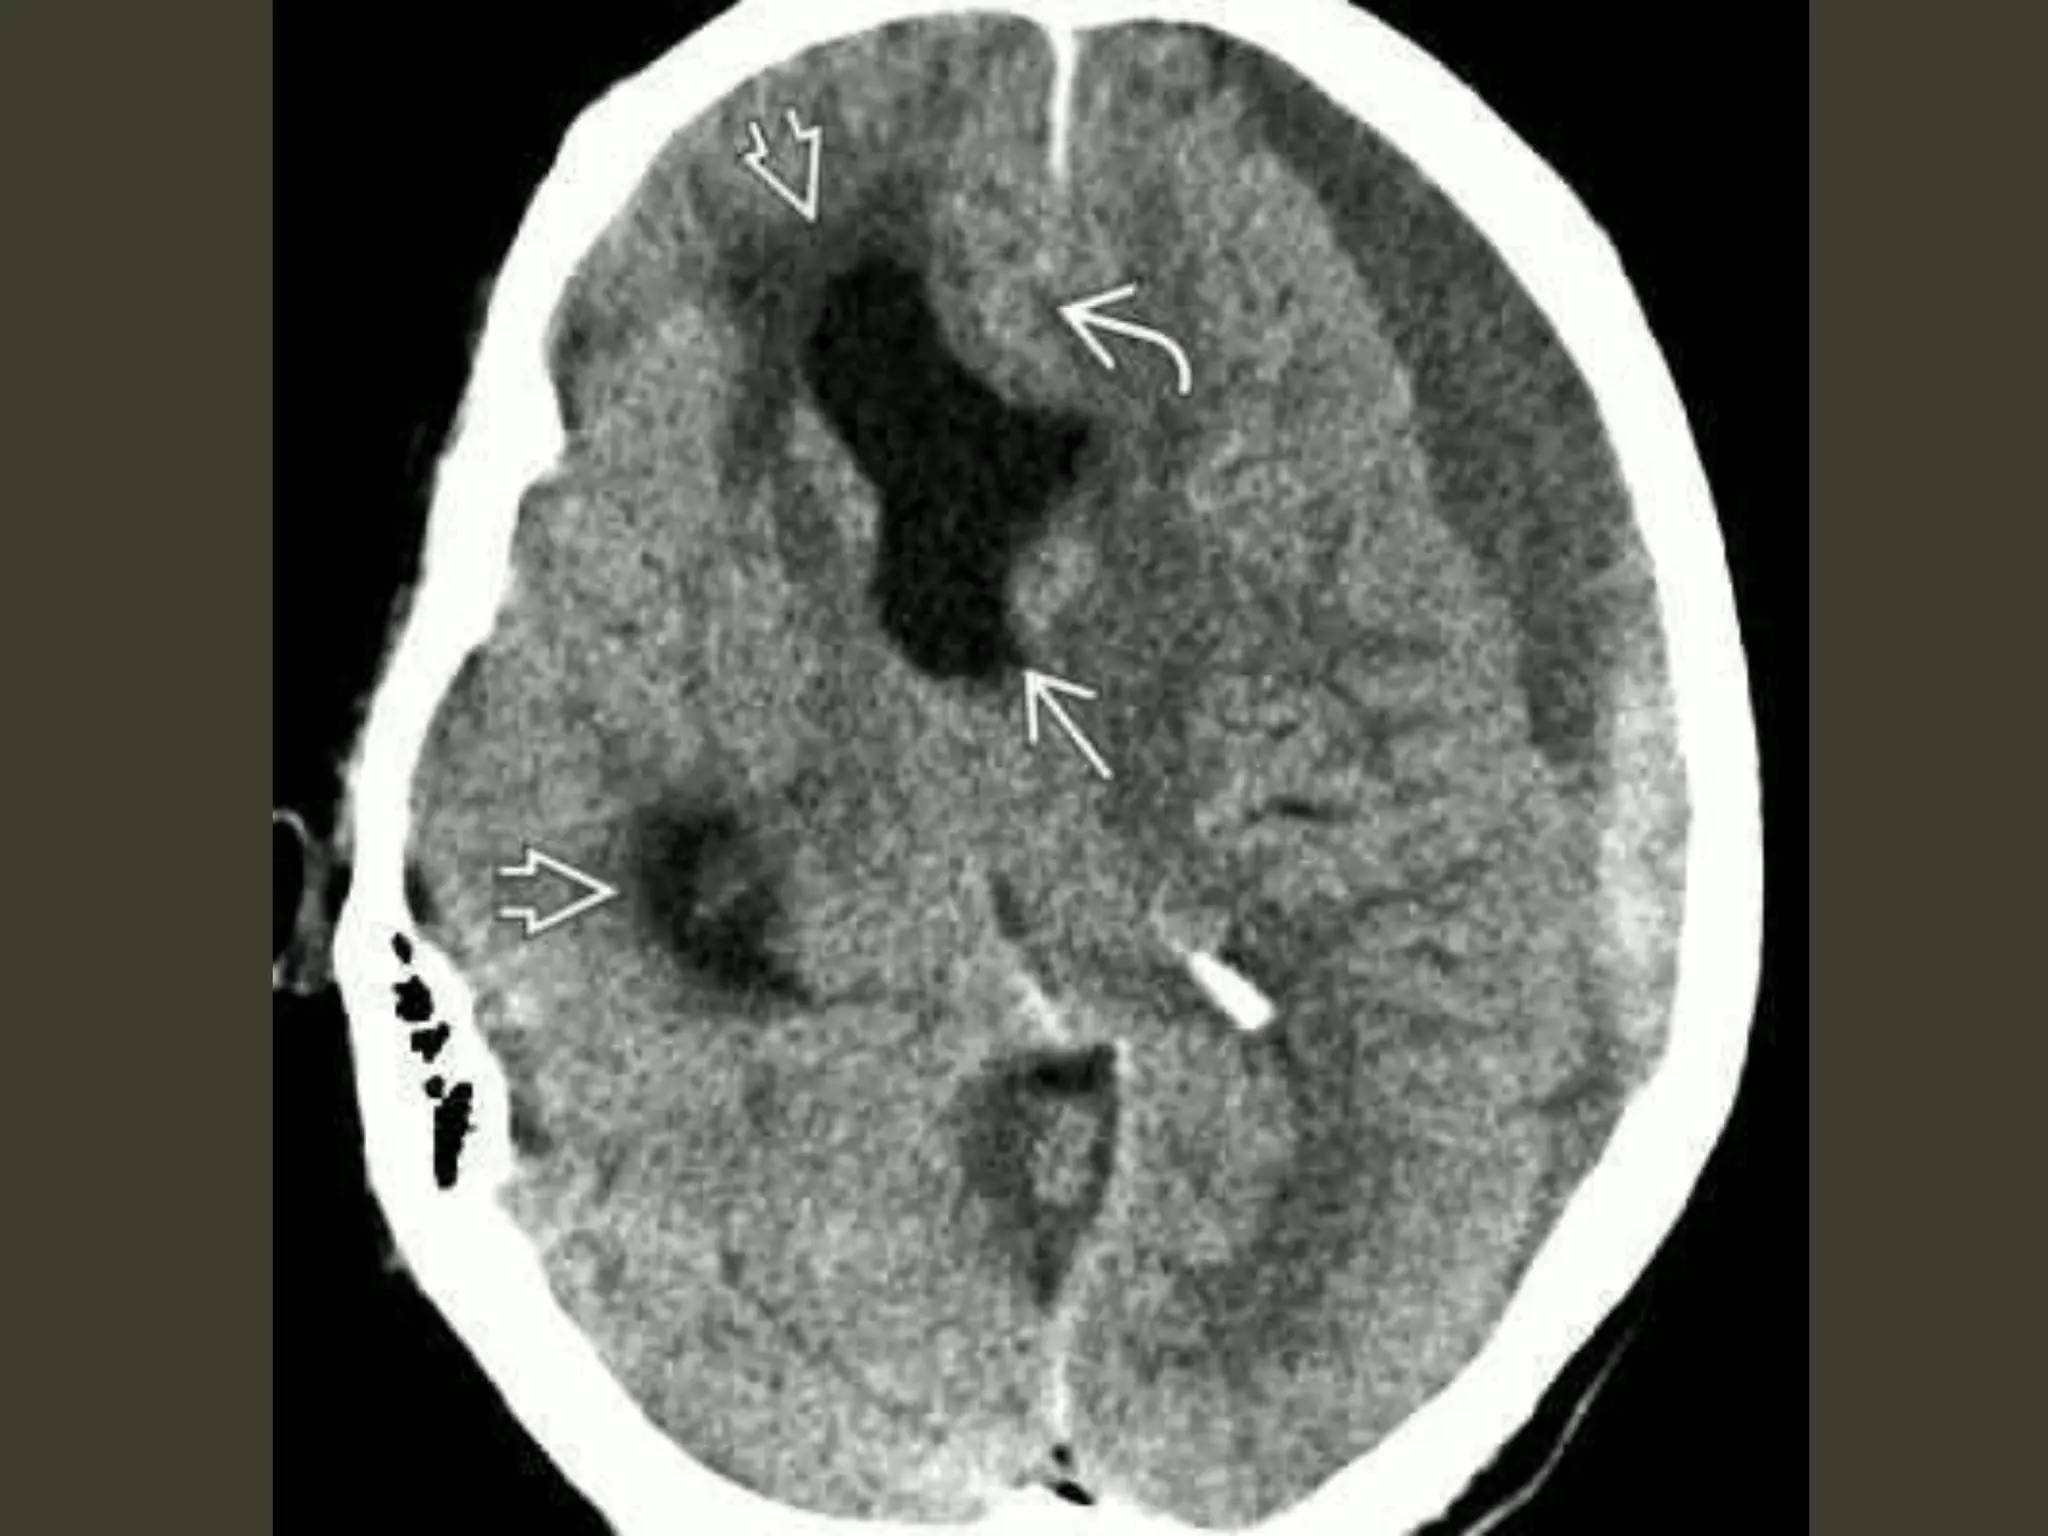

Descending transtentorial

herniations• the second most common

• a hemispheric mass

• initially produces subfalcine herniation

• As the mass effect increases,

the uncus of the temporal lobe is pushed medially

begins to encroach on the suprasellar cistern

hippocampus follows

hippocampus effaces the ipsilateral quadrigeminal

cistern

both the uncus and hippocampus herniate inferiorly

through the tentorial incisura

unilateral DTH: imaging

early

uncus is displaced medially

Ipsilateral aspect of the suprasellar cistern

effaced

Ipsilateral prepontine + cerebellopontine angle

cistern enlarged

herniation

As DTH increases

hippocampus also herniates

medially

quadrigeminal cistern

compression midbrain pushed

toward the opposite side of the incisura

severe cases

entire suprasellar and quadrigeminal cisterns

are effaced.

The temporal horn can even be displaced almost

into the midline